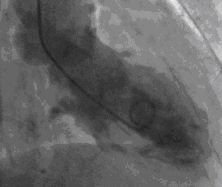

Cardiac catherization on hospital day 15 revealed normal coronary arteries (Figure 1) with anterobasal and posterobasal hyperkinesis, anterolateral and diaphragmatic hypokinesis, and distal ballooning on ventriculography. Ventriculography revealed global LV depression with EF of 45% (Figures 2, 3).

Fig3

Figure 3-The end systolic frame of left ventriculogram shows basal contraction with distal ballooning